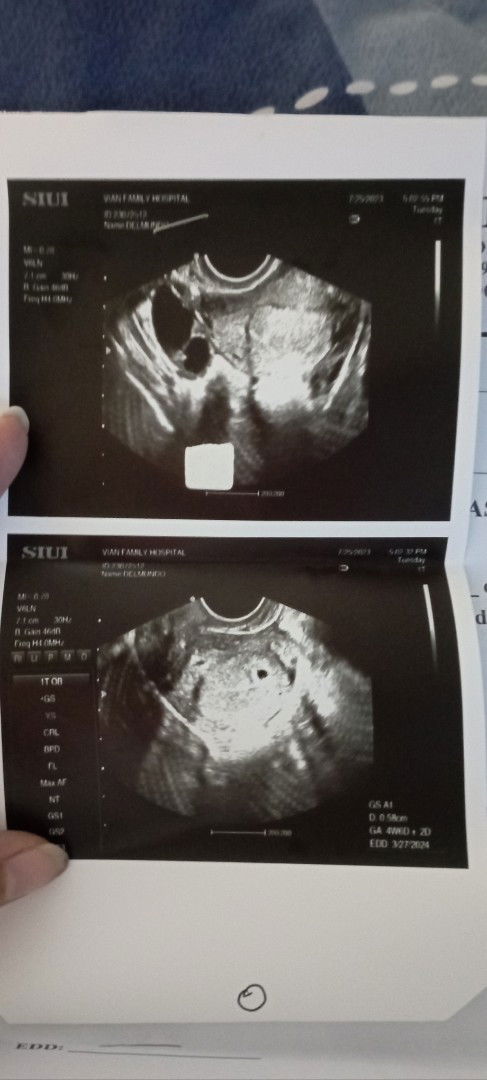

it may mean early pregnancy. babalik after 2weeks to check kung kita na si baby. always pray while waiting. ako, 10weeks sa LMP pero 7weeks sa ultrasound. kita si baby.